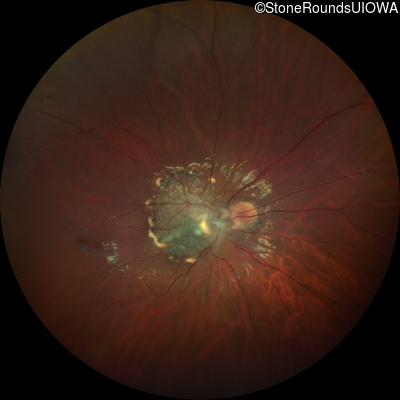

This 9 year old male was noted to have some crossing of his eyes at 2 months of age and the eye exam which followed identified a retinal lesion in the right eye. When he was six years old an epiretinal membrane was noted in his left eye. Two years later it was decided that it was a thin hamartoma in that eye as well. He underwent neuroimaging at age 7 which identified bilateral acoustic neuromas.

| Age at visit: 8 years |

| Age at visit: 10 years |

| Age at visit: 11 years |

| Age at visit: 14 years |

| Neurofibromatosis | NF2 | Trp258 del1tG | AD |